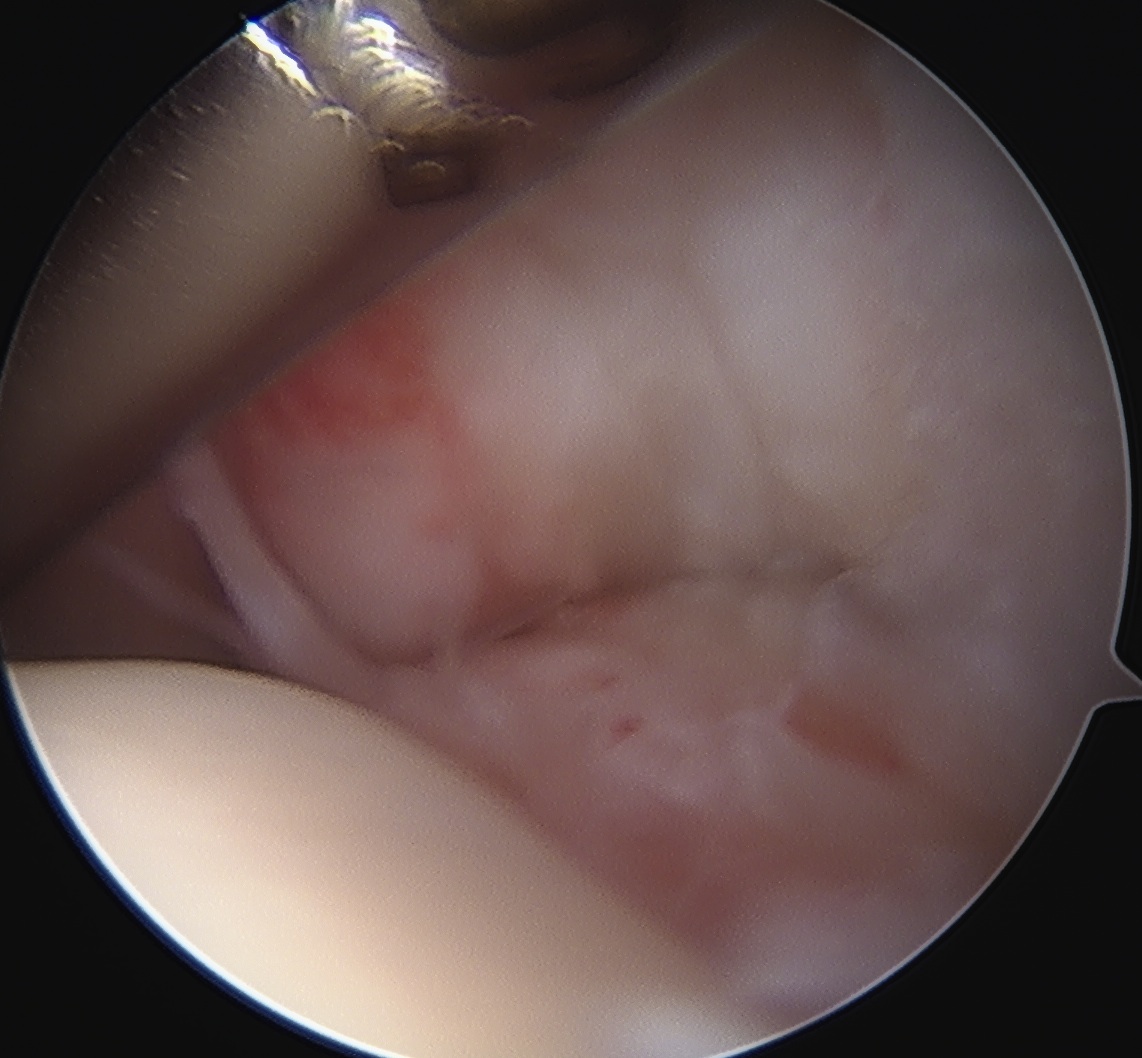

Articular side

Normal insertion of undersurface of the rotator cuff onto the footprint, with camera in glenohumeral joint

> 50% uncovering of footprint in glenohumeral joint